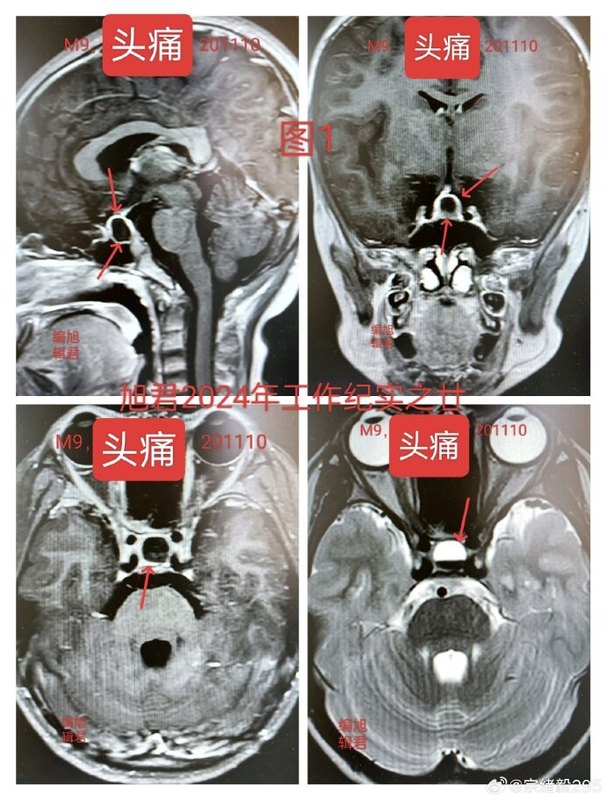

一位10歲的患者,一年前因持續(xù)頭痛4個(gè)月,到醫(yī)院就診,經(jīng)過MR掃描,發(fā)現(xiàn)鞍區(qū)占位,考慮為垂體腺瘤并伴隨卒中,見下【圖-1】,激素檢查顯示泌乳素水平高出正常值10倍。一、診斷:泌乳素型垂體腺瘤二、處理方案:1、根據(jù)專家共識(shí),首選藥物治療泌乳素型垂體腺瘤。2、也可考慮手術(shù)切除,因卒中的腫瘤質(zhì)地較軟,易于完全切除。與家屬充分溝通,并經(jīng)過神州考慮之后,家長認(rèn)為既然藥物治療有效、副作用輕,便首選藥物治療。按泌乳素腺瘤治療專家共識(shí),最初每日服用1片,分兩次,第四天增加至每日2片,持續(xù)八個(gè)月。兩個(gè)月后泌乳素水平顯著下降,但仍高于正常值2倍,繼續(xù)服藥兩個(gè)月后未見進(jìn)一步下降,于是增加劑量至每日3片。然而,泌乳素維持在正常上限2倍,未進(jìn)一步下降。復(fù)查MR顯示腫瘤基本消失,見下【圖-2】。三、現(xiàn)狀及考慮:泌乳素水平仍高于正常上限,服藥劑量已達(dá)最大劑量的一半,且孩子年僅10歲,而復(fù)查顯示腫瘤基本消失。此時(shí)的最佳處理方案是什么?該病例中,患者泌乳素水平超出正常上限10倍,臨床上單純藥物治療效果一般較差。盡管按專家共識(shí)選擇了藥物治療,取得了一定效果,但結(jié)果并不完全理想。如果當(dāng)時(shí)首選手術(shù)切除會(huì)如何?旭君個(gè)人傾向手術(shù)切除可能更為有利。